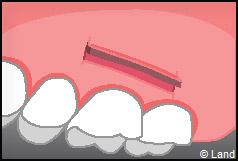

LES TECHNIQUES AVEC APPORT DE GENCIVE OU « GREFFE DE GENCIVE » :

Elles font appel à un prélèvement sur le patient à un endroit où elle est en excès, qui est ensuite posé sur la récession.

Les greffes épithélio-conjonctives :

Elles sont pratiquées pour des zones non esthétiques de la cavité buccale, à cause de l’aspect « rustine» que la cicatrisation leur confère.

Destinées aux zones esthétiques, elles consistent à prélever la partie profonde du palais (site donneur).